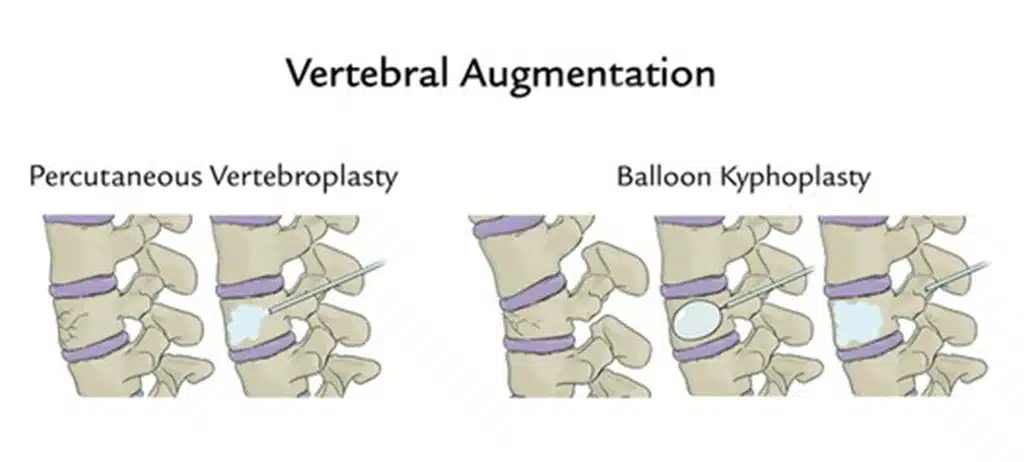

Below is a brief overview of how some of the more common geriatric fractures are managed, and what you can expect during these treatments.